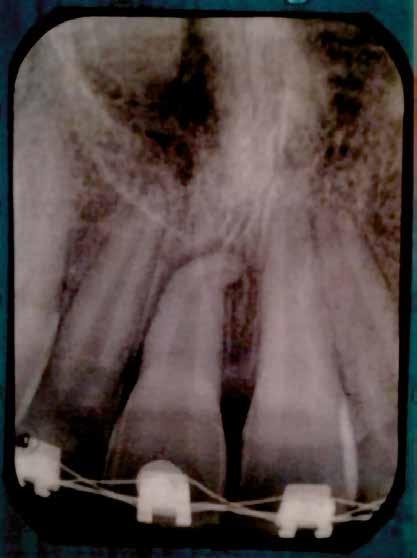

A 10 éves férfi páciens a felső frontfogai késői/nem megvalósuló előtörése miatt kereste fel a rendelőnket. A klinikai és a radiológiai vizsgálat során a jobb felső nagymetszőfog impakcióját észleltük (1. ábra). A fog horizontális tengelyállással és dilacerált gyökérrel rendelkezett. A felső dentális középvonal a fogak vándorlása miatt jelentős mértékben elcsúszott. A bal felső kismetszőfog is rendkívül kedvezőtlen pozícióba került.

Dr. Kazem Dalaie, dr. Samin Ghaffari, dr. Mazir Mir (Irán, Németország) 1. a ábra: Az intraorális felvételen jól látható a jobb felső nagymetszőfog lehetséges impakciójára utaló foghiány.

1. b ábra: A panoráma röntgenfelvételen megfigyelhető a teljes impakcióban lévő jobb felső nagymetszőfog. 1. c ábra: A CBCT felvétel is igazolja a jobb felső nagymetszőfog impakcióját.

sok korrigálása, valamint az impaktálódott fog előtöréséhez szükséges hely megteremtését követően, egy merev acél ív segítségével stabilizáltuk a fogakat. Ezt követően elvégeztük a jobb felső nagymetszőfog sebészi feltárását. A fog koronáját csupán lágyrész borította, ezért nem volt szükség a csontállomány elvételére. A felszabadítás során egy 975

nm-es hullámhosszon pulzáló üzemmódban alkalmazott lézert használtunk (LaserHF standard, Hager & Werken). A teljesítménye 3 W, az aktív ciklus-idő 50%-os, a vezetőszál átmérője pedig 0,4 mm volt (2. ábra). A lézert 150 másodpercen keresztül alkalmaztuk. A fogat borító lágyrészek eltávolítását követően egy láncos brekettet rögzítettünk a metszőfog bukkális felszínére. A műtétet követően nem tapasztaltunk vérzést, nem alakult ki oedema, valamint a páciens sem számolt be fájdalom vagy bármely egyéb kellemetlenség fennállásáról. A felszabadítást követően a páciens minden hónapban háromszor jelent meg a felszabadított területre ránövő lágyrészek és az íny lézeres eltávolítása céljából. A beavatkozások során ugyanazt a lézer készüléket használtuk, mint amivel a felszabadítást végeztük. Közvetlenül a felszabadítást követően megkezdtük a fog finom extrudálását a láncos breketthez kötött füzérgumi segítségével.

2. ábra: Az impaktált fog lézerrel asszisztált sebészi feltárása. 3. ábra: A kezelés megkezdését követő 15. hónapban megfigyelhető a sikeres felszabadítást, fogmozgatást és pozicionálást követően látható állapot.

4. a ábra: A CBCT felvétel igazolja, hogy a jobb felső nagymetszőfog megfelelő pozícióba került. Az ínyszél lefutása kedvező, a fog gyökere körül elfogadható mennyiségű csontállomány ábrázolódik, valamint a gyökérfelszívódás mértéke sem túl kifejezett.

6 hónapon keresztül tartott. Ennek megfelelően a fog körül található szövetek a felszabadítás, valamint a havi kontrollok során 975 nm-es (több mint 25 J/cm2 energiasűrűség) és 660 nm-es hullámhosszúságú (12–18 J/cm2 energiasűrűség) lézersugarakkal is megvilágításra kerültek. Az impaktálódott fogat megközelítőleg 7 hónap alatt tudtuk megfelelő pozícióba mozgatni (3. ábra). Az orthodoncia kezelés aktív szakasza 18 hónapon keresztül tartott. A fogívek végső nivellálását és a fogak végleges pozícióba rendezését 0.018 × 0.025-ös acélívekkel végeztük.

A kezelés befejezésekor a páciens mosolya drámai mértékben javult, továbbá a frontfogak elhelyezkedése és az ínyszél lefutása is szemmel látható módon kedvezőbbé vált (4. ábra). A kezelés végén készült CBCT felvétel nem mutatta

csontfelszívódás jelenlétét, és csupán minimális mértékű gyökérfelszívódás bekövetkezését igazolta.

4. b ábra: A panoráma röntgenfelvétel is alátámasztja a CBCT felvételen látottakat. 4. c ábra: Az intraorális felvételen megfelelő fogpozíciók és kedvező ínyszéli lefutás ábrázolódik.

A lézerrel asszisztált felszabadítás előtt készített felvétel.

A végső állapotról készült periapikális felvétel.